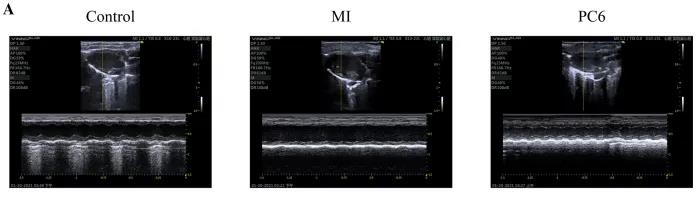

成年雄性C57BL/6雄性小鼠隨機分為對照組、MI組和PC6組。MI組小鼠為通過結(jié)扎冠狀動脈左前降支(LAD)形成MI模型,PC6組在造模完成后,針刺內(nèi)關(guān)穴治療5天后取材。經(jīng)胸超聲心動圖評估MI手術(shù)前后小鼠心功能情況,并進行血清心肌酶和炎癥細胞因子的測定,之后三組樣本各取3個重復(fù),共9個樣本進行ONT全長轉(zhuǎn)錄組測序。

為了探討針刺PC6穴對心肌損傷的影響,作者首先評估了心功能和梗死面積。超聲心動圖結(jié)果顯示MI組的EF(ejection fraction)和FS(fractional shortening)均較對照組明顯降低。PC6穴位治療后,EF和FS均增加。針刺治療5天后, 采用TTC染色檢測梗死面積。結(jié)果顯示,針刺治療顯著減小心肌損傷的大小。采用ELISA法測定反映急性心肌損傷的心肌特異性血清酶,包括心肌肌鈣蛋白T (cTnT)和心肌肌鈣蛋白I (cTnI)的水平。結(jié)果表明,心肌梗死術(shù)后cTnT和cTnI水平升高,針刺可顯著降低血清酶水平。